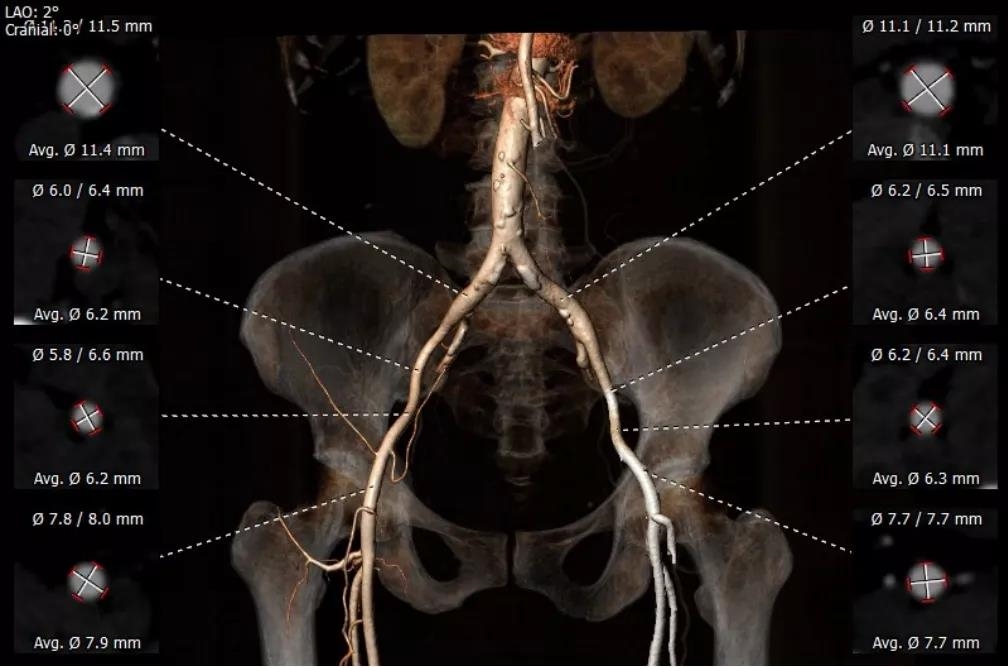

术前经详尽影像学重建和评估,CT重建测量瓣环直径,评估冠脉梗阻风险及外周血管条件。最终采用经股动脉入路植入21# Renato球扩式瓣中瓣。手术顺利,瓣中瓣植入位置理想,功能表现出色,主动脉瓣峰值流速由术前4m/s下降至2m/s,平均跨瓣压差由术前40mmHg下降至6mmHg。经食道超声观察无瓣周漏及瓣中反流。